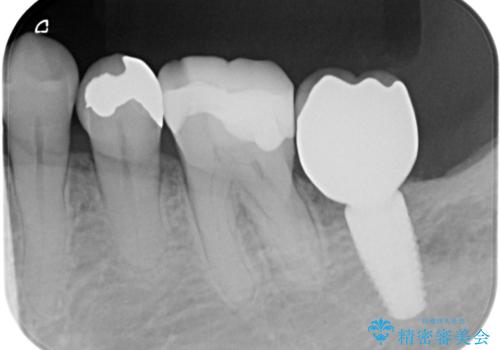

- 半分残していた奥歯の虫歯の状態が良くない為、抜歯をしてインプラントをしました。

向かい合わせの歯の治療も、神経の治療からセラミックのかぶせ物まで行っています。

- 69.4万円 内訳:左下7(ストローマンインプラント24.2万円 インプラント用仮歯2.2万円 骨増成5.5万円 カスタムアバットメント11万円 FGG(遊離歯肉移植術)11万円 静脈内鎮静5.5万円)費用は治療当時の料金となります

他の歯の治療もあり治療に時間をかけることが問題なかった点、また、審美領域ではない点、患者様が時間をかけてもいいのでお手入れしやすく長持ちするインプラントを希望していたことから2回法を選択しております。一回法のメリットは今回は特にありませんでした。患者様のご希望もふまえ、無理せず抜歯後しっかり骨ができるのを待って、角化歯肉を増やすため歯肉移植も行いました。